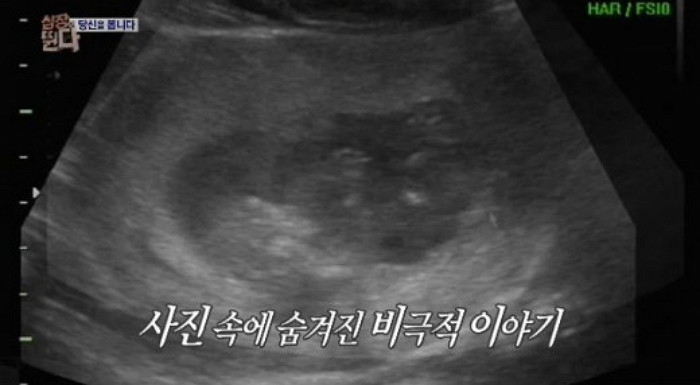

때는 지난 2014년, 한 여성은 임신 7개월 차였고 그녀에게 갑작스레 위급한 상황이 찾아왔다.

뱃속에 있는 아이의 생명이 위독하던 차라 인큐베이터가 있는 병원으로 한시라도 빨리 가야만 했다.

이렇게 실갱이를 하는 동안 뱃속의 아이는 그대로 방치되었고, 결국 아이는 세상의 빛을 보지 못했다고 한다.